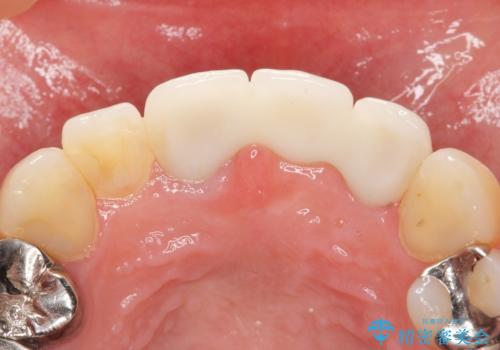

古いブリッジと金属の土台を除去し、ファイバーコア(金属を使わない強くてしなやかな土台)を植立したのち、オールセラミックのブリッジによる補綴治療を行いました。。

- ¥385,000 (土台×1本、仮歯×3本、クラウン×3本) ※税込費用は治療当時の料金となります

クラウンの種類:オールセラミッククラウン スタンダード